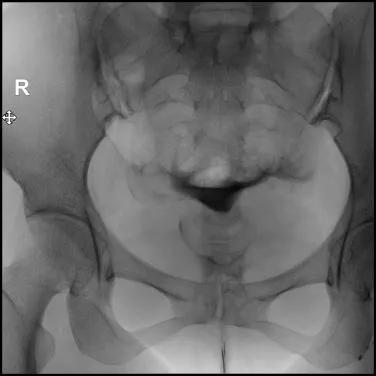

9.在注入对比剂后的20分钟或24小时再拍一张弥散片,观察对比剂在盆腔的弥散情况,分析宫颈、子宫、输卵管的形态特征;

弥散片